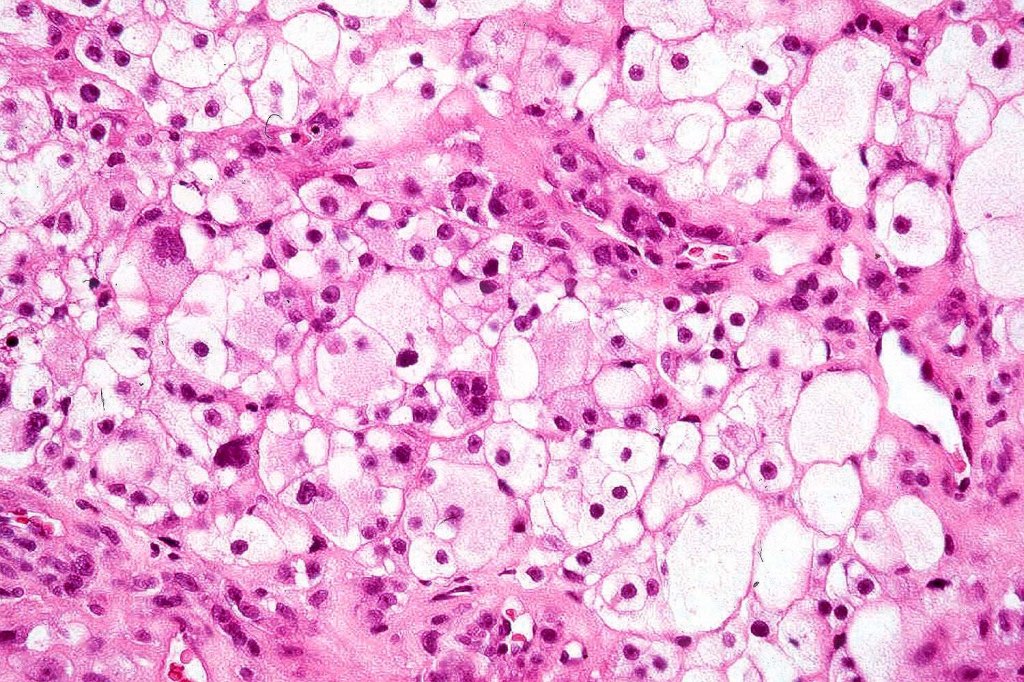

Histological features

•May affect the tumor in part or whole

•Enlarged cells with copious eosinophilic, foamy or clear cytoplasm (some authors include melanoma with clear cell change in the same category)

•Variable pigmentation

•Nuclei vesicular or hyperchromatic

•Pleomorphism is not generally marked and indeed can be very subtle

•DPAS granules

•Thought to be a result of abnormal or degenerative melanosome change